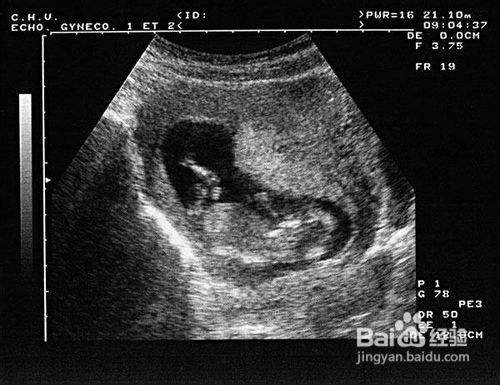

二、做B操是安全的

一般来说,你不用这么紧张,B超是一项对胎儿非常安全的检查方式。你可以在孕期按时接受产前检查,及时了解宝宝的发育情况。重要的是,放松心情对你和宝宝是非常有好处的。